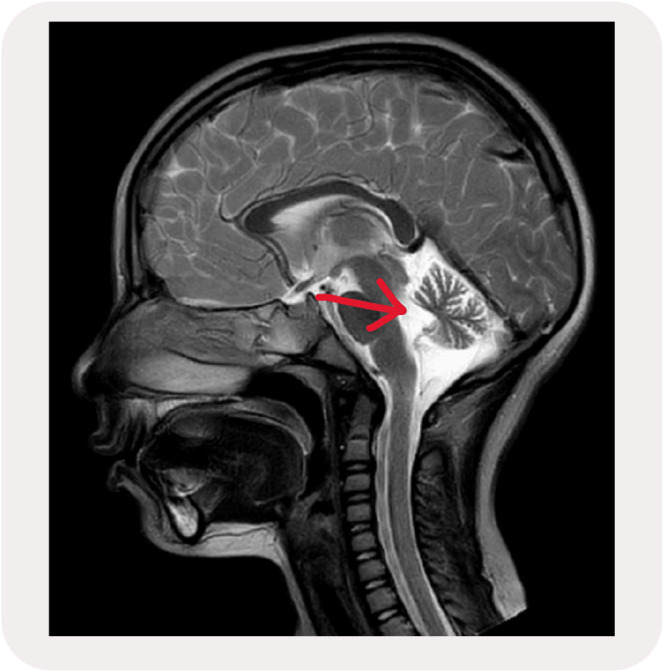

Ataxia telangiectasia (AT) is a rare neurodegenerative condition with a prevalence of 1 in 40,000 to 1 in 300,000 worldwide. It involves a genetic mutation of chromosome 11q.26. The condition is inherited in an autosomal recessive manner causing atrophy of the cerebellum due to loss of Purkinje fibres. AT presents early in childhood and the clinical features depend on the type of mutation. The study is a case report of a rare genetic disorder of a 9-year-old female who came to the physiotherapy clinic with a diagnosis of AT. The patient was presented with progressively worsening gait problems with frequent falls, with complete dependence on assistance and impaired balance and coordination. The treatment program was 12 months divided into an intense physiotherapy program for two months followed by 10 months of two times per week of physiotherapy sessions. The program was divided into four elements which are: (1) Lifestyle changes, (2) Strengthening exercises, (3) Coordination exercises, and (4) Balance training exercises. The result showed a positive outcome in increasing the patient's independence, increased muscle strength, reduced ataxia symptoms intensity, and the patient can carry out complex activities with the help of accessory orthosis devices.